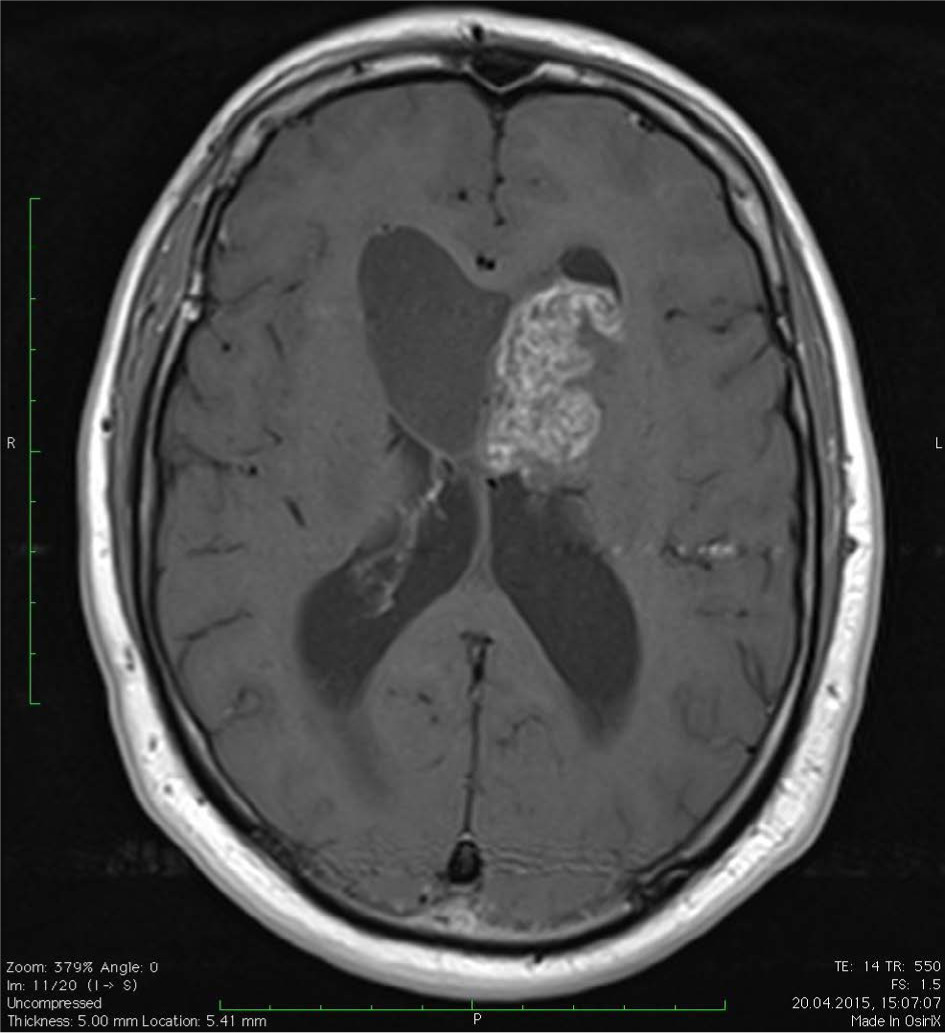

An MRI scan showed an irregular mass in the frontal horn of the left lateral ventricle and a nodular lesion with a cystic appearance in the frontal horn of the right lateral ventricle (Figure I). The maximum size of the cysts was approximately 46 mm, with a solid portion of 43 mm. The tumor was hyperintense with variable contrast enhancement. The tumor mass was shown to compress the foramen of Monro, resulting in an enlargement of the lateral ventricles.

Figure I

Subependymoma. Preoperative MRI image showing an intraventricular tumor arising from the ventricular wall. Axial post-contrast T1 imaging